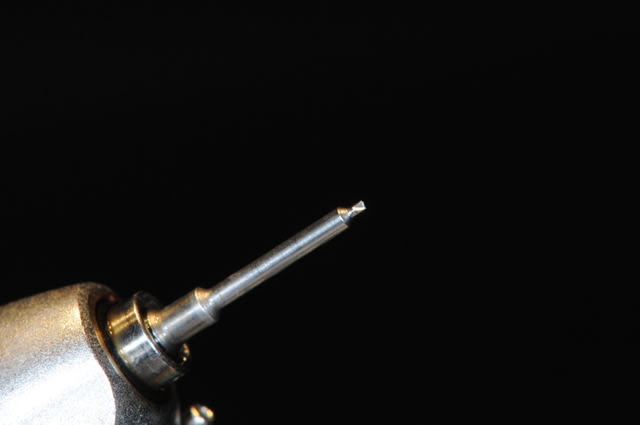

1: foret de perçage pour que l'os puisse apporter du sang.

(initialement, c'est un foret pour les pins densply)

5-6: le foret de mise en place des vis et le foret destiné à faire un pré-perçage